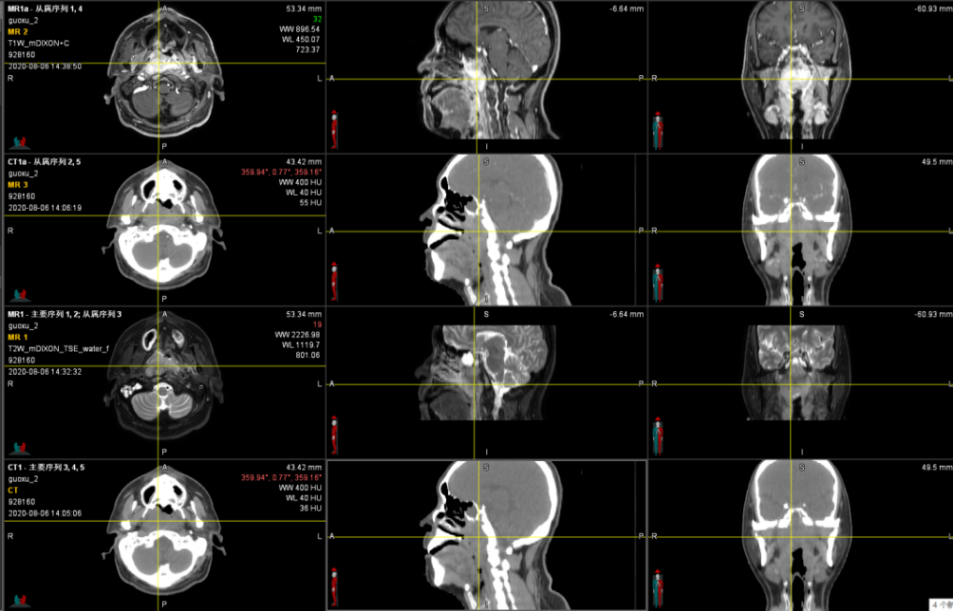

图2-3为一鼻咽癌患者MR-CT融合定位 3D扫描,其鼻咽部病灶在MR上肿瘤边界清晰,在勾画靶区过程中MR的增强、CT平扫、CT增强融合配准后3维立体同步联动,大大提高了靶区的精准性。

图2鼻咽癌MR vs CT

图3MR-CT融合定位3维立体定位肿瘤